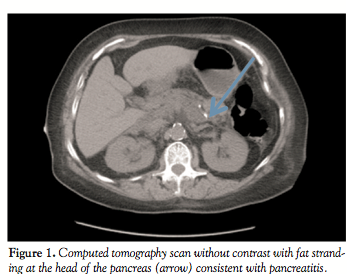

level was within the normal range at 62 mg/dL. Her creatinine was normal and remained unchanged during her hospitalization. An abdominal computed-tomography scan without contrast was consistent with acute pancreatitis (Figure 1) with no evidence of gallstones. The patient was managed with empiric antibiotics, intravenous fluids, nutritional support and mechanical ventilator support for the subsequent development of acute respiratory distress syndrome. The patient’s condition improved after the initial 48 hours. As part of the in-hospital work-up, common causes of acute pancreatitis, such as medication, alcohol, hypertriglyceridemia, and gallstones were dismissed. Other uncommon causes of pancreatitis, such as autoimmune pancreatitis, were ruled out by identifying a negative ANA and normal IgG1-4 titers. At discharge a few days later, she was asymptomatic and amylase and lipase levels were 65 U/L and 56 U/L, respectively.